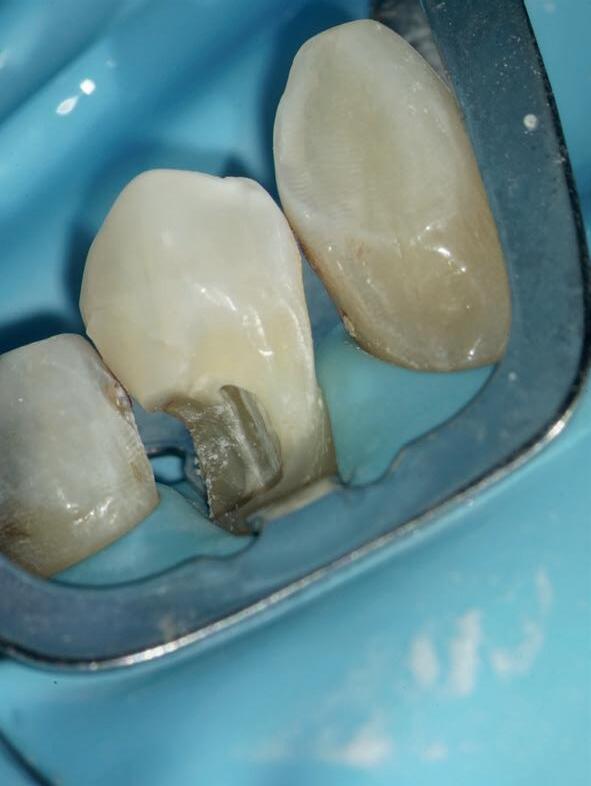

Stap 3: Kies de matrix

Kies de juiste hoogte matrixband van het V3 systeem. Ideaal gezien steunt de matrixband op het tandvlees en eindigt de bovenzijde van de matrix ter hoogte van de randlijst van het element (afbeelding 5).

Stap 4: Plaats de gemodificeerde wig

Plaats een afgeknipte wig. In bijna alle gevallen gebruik ik de Wizard Wedge Wide base. Hierbij is het belangrijk dat de wig geplaatst wordt aan de zijde waar het minste tandweefsel verloren is gegaan. Zorg ervoor dat de wig direct vastloopt. Indien dit niet het geval is, dan dient de wig ingekort te worden met behulp van een schaartje en opnieuw geplaatst te worden. De wig sluit dus de bodem van de box niet af, zoals je normaal gesproken met een wig wel doet (afbeelding 6 en 7).